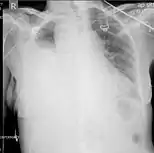

CT scan of the chest showing a hemothorax caused by warfarin use

Computed tomography (CT or CAT) scans may be useful for diagnosing retained hemothorax as this form of imaging can detect much smaller amounts of fluid than a plain chest X-ray. However, CT is less used as a primary means of diagnosis within the trauma setting, as these scans require a critically ill person to be transported to a scanner, are slower, and require the subject to remain supine.[23][26]